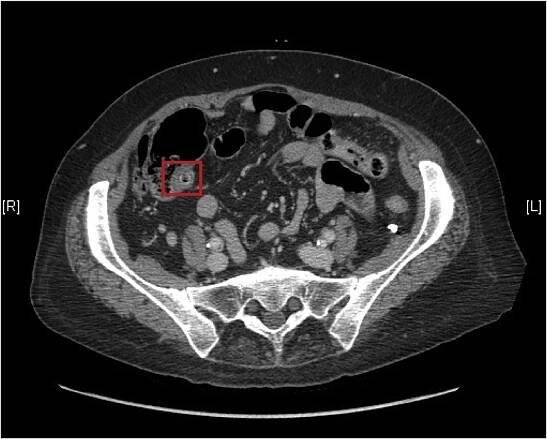

Peritonitida je zánět pobřišnice (serózní membrány, která obaluje část dutiny břišní a některé břišní orgány). Může být lokalizovaná nebo generalizovaná, obecně má akutní průběh a může být způsobena buď infekcí (často z ruptury dutého orgánu, například při poranění břicha), anebo neinfekčním procesem.